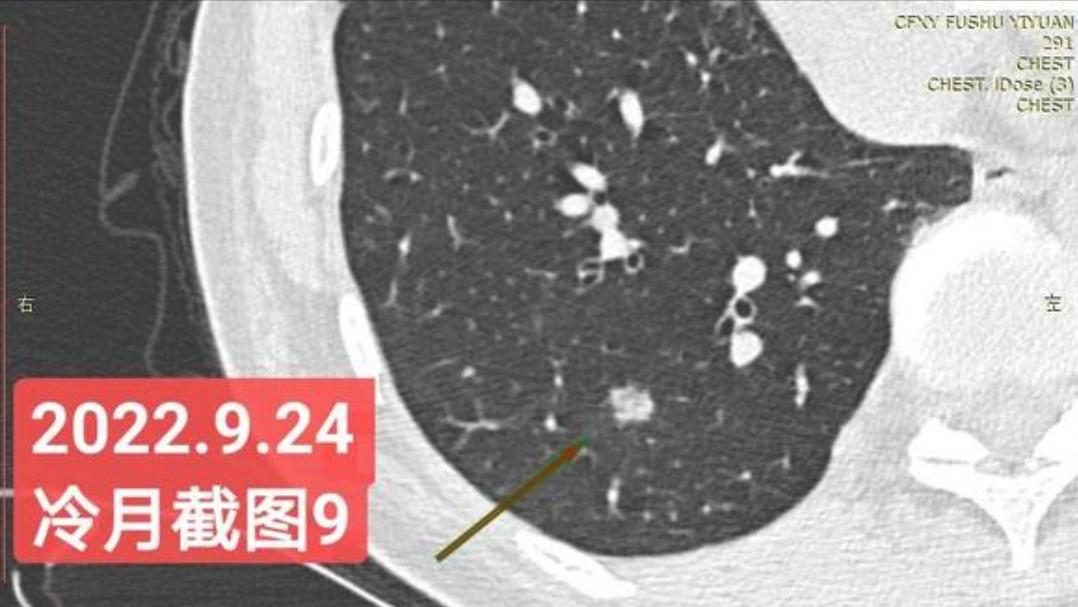

我是21年7月做肺部CT,报告给报出0.5厘米肺结节。(但大夫说,20年就已经有那个肺结节了,因为小,报告没给报)。自发现肺结节后,吃了四个月中药,结节没有缩小,反而增大了。今年8月1日开始到现在,又吃了近两个月的蒙药了。 结节还是没有缩小,反而在增大。21年7月到现在,复查过3次肺部CT了。结节一直在增大。最近一次复查时间是2022年9月24日。

上次找戴主任贴吧咨询过,主任说我右肺下叶那个结节高危,距离上次CT,到现在三个月复查肺部CT。所以9月24日又复查做了肺部CT。

1.请主任看看我高危结节有哪几个?分别在什么位置?大小都是多少?分别是实性、纯磨还是混合磨玻璃?都分别处于哪个阶段(原位、微浸润还是浸润)?密度分别是多少?

右下肺结节高危,肺窗已经到亚实性阶段CTR>0.5,纵膈窗可见实性,目前已经不属于异质混磨,而且PSN亚实性结节。